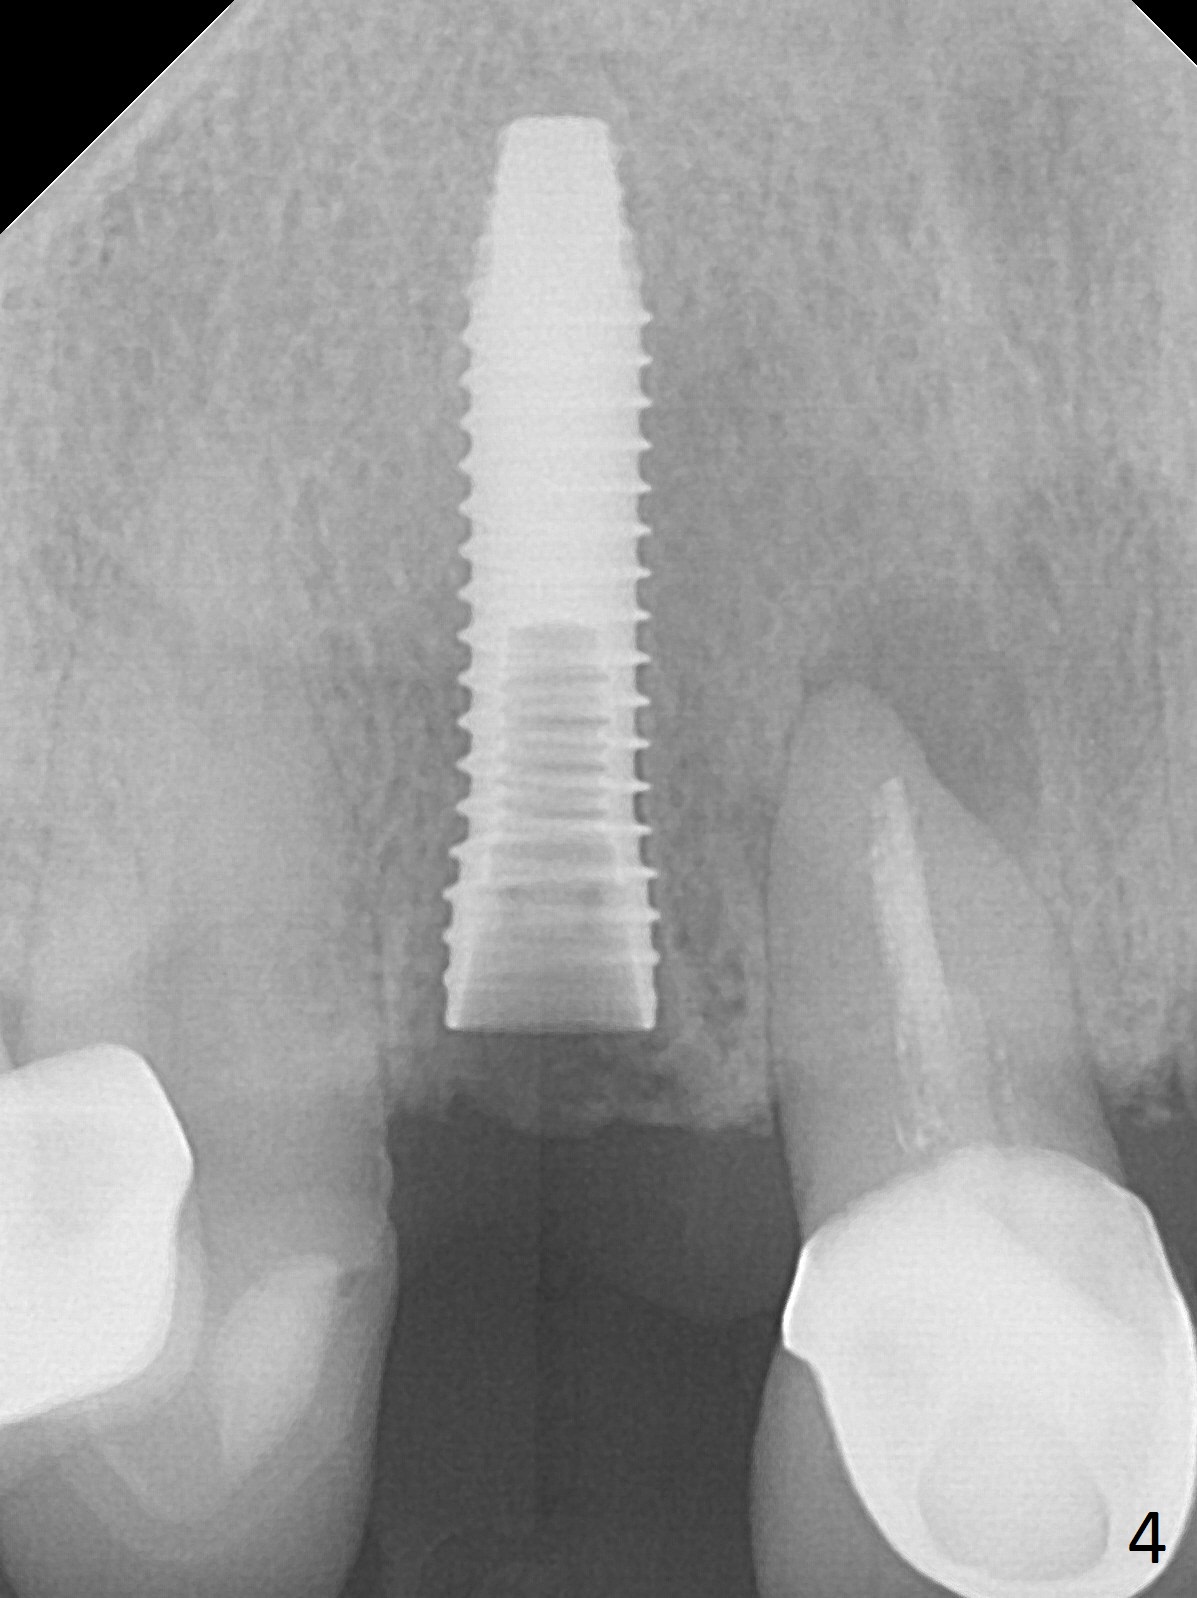

In fact the residual root (Fig.3) is easy to remove. A 3.8x16 mm implant is placed (Fig.4 (with 2 mm buccal gap)) at the level as planned (Fig.2). Insertion torque is acceptable. After placing a 4.5x5(3) mm gold-coated abutment and allograft (Fig.5), an immediate provisional is fabricated (the existing crown is lost). The patient is pleased with the quick, painless procedure.